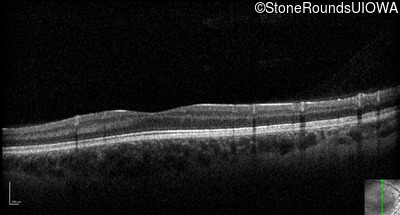

Optical Coherence Tomography - Right - 10/160 +1 sc

Exemplar / OCT Stack

OCT Stack